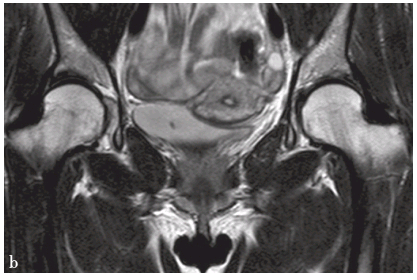

双侧髋臼发育不良

a. MRI横轴位T1WI,示前断面角变小;b.冠状位T2WI,示髋臼稍变浅,Sharp角增大

髋臼窝浅平,冠状位示Sharp角增大,横断位前断面角及后断面角皆变小。顶唇和(或)前后唇短小;髋臼前上缘骨质增生,呈短T1及混杂短T2低信号;髋臼前上缘或上缘软骨下可见单囊或多囊灶,呈长T1或稍长T1低信号、长或稍长T2信号,抑脂像上呈高信号。关节内有时可见长T1、长T2积液。